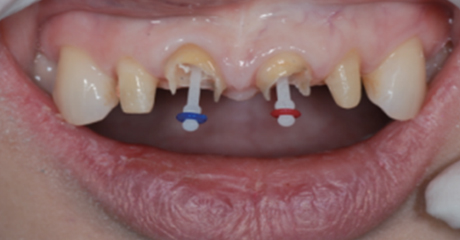

치아의 길이가 너무 짧은 경우는 치아의 길이를 늘리는 수술이 필요하기도 합니다.